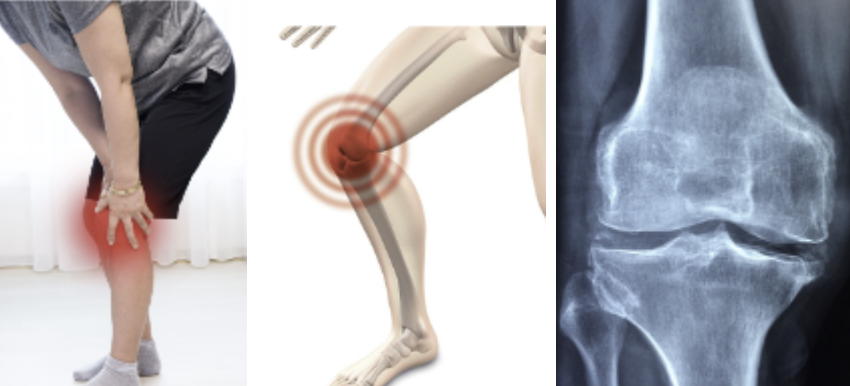

3단계: 연골 손상이 더 진행되며 뼈가 뾰족하게 자라 통증을 유발하는 단계입니다. 외관상으로 부기가 관찰될 수 있으며, 조금만 걸어도 무릎 통증이 발생합니다. 무릎에서 뚝뚝 거리는 소리인 '염발음'이 들리며 때로는 고관절에서도 소리가 날 수 있습니다. 연골이 사라지면서 관절 끝이 비정상적으로 마모되어 뼈와 뼈의 마찰로 인해 극심한 통증이 나타나며 운동을 하지 않는 경우 관절이 경직되어 무릎이 아파지는 정도가 더욱 심해질 수 있습니다. 특히 어깨, 팔꿈치, 손목과 같은 위치의 관절염과는 다르게 무릎 관절염증의 경우 체중의 힘을 직접적으로 전달받기 때문에 통증이 심하며 이러한 통증으로 인해 걸음이 불편해져 절뚝거리거나 잘 걷지 못하는 '보행 장애'가 나타나기도 하며 그 결과 '근육의 위축'으로 이어질 수 있습니다.

4단계: 연골 손상이 매우 심해 무릎 관절의 뼈와 뼈 사이가 매우 좁아 거의 맞닿은 상태입니다. 무릎 통증이 심하고 붓고 열감이 있으며 야간통이 있습니다. 일주일에 4일 이상 무릎 통증으로 인해 잠이 깨는 증상이 있거나, 외관상 다리가 O자로 휘어져 있거나, 계단 내려갈 때 무릎이 아파 주저앉고 싶은 경우, 평지에서도 절뚝거리며 걷는 증상이 나타나는 경우가 대표적인 예입니다.